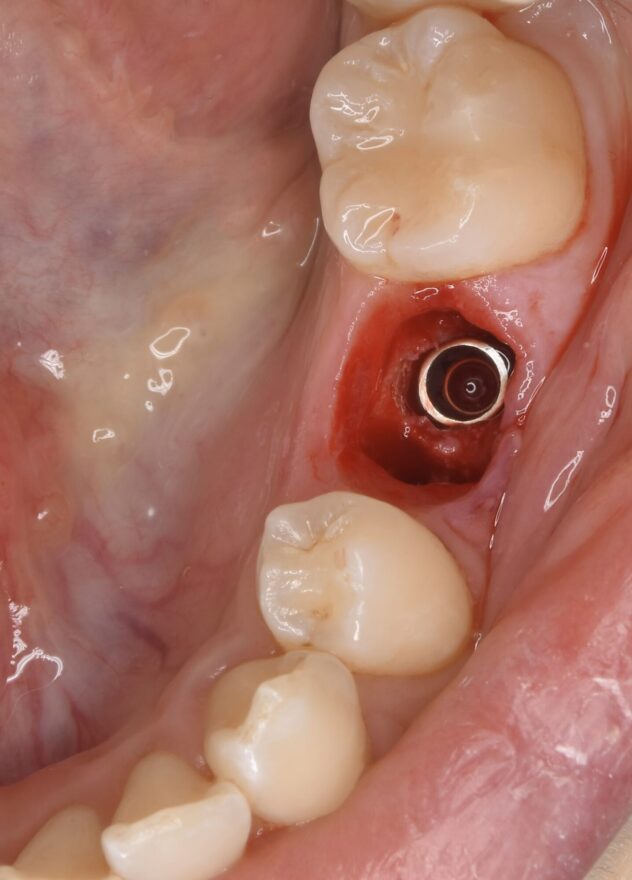

①乳歯を抜歯してのインプラント埋入。

②インプラントに仮歯のセット。

インプラント治療の口腔内写真

ここまでのオペ時間はわずか10分。

もちろん痛みと腫れもありません。